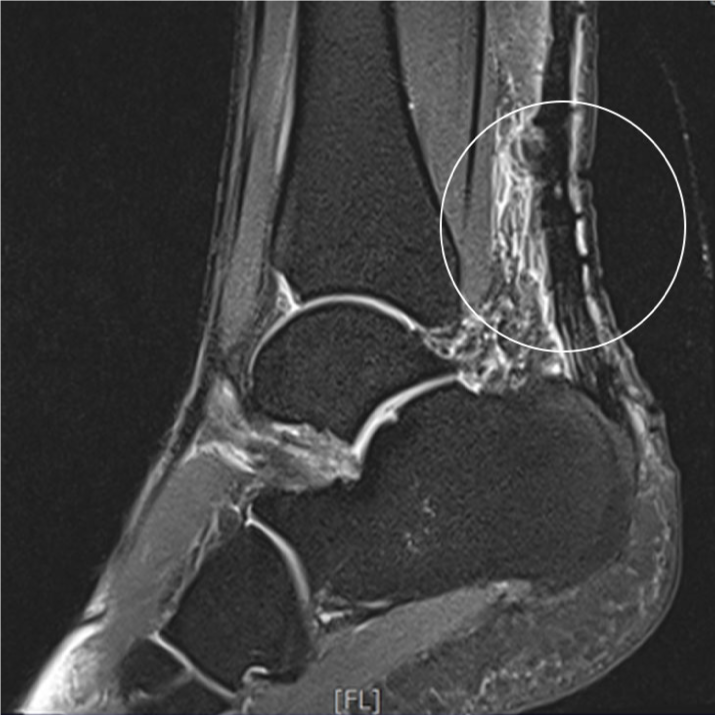

아킬레스건 파열 봉합술 전후 아킬레스건 근전 접합부 완전 파열 및 동반된 종파열

• ㆍ수술 30분~1시간

• ㆍ입원 3~4일

• ㆍ4주간 깁스 착용

• ㆍ보조기 착용